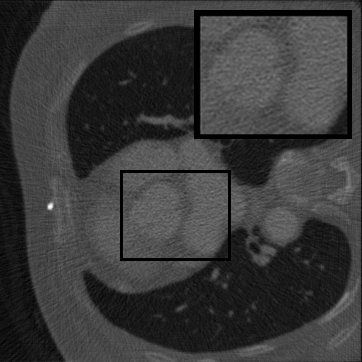

Figure 2: Qualitative inpainting results on TomoBank (lines 1 to 2) and LoDoPaB (lines 3 to 4) with random mask (ratio = 0.8) at 1024×\times1024 resolution. Odd columns and even columns show the sinograms and reconstructed images, respectively.

Inpainting Quality. Tab 2 summarizes accuracy results. At 2048×\times2048 resolution, HiSin achieves the best performance among all baselines while remaining memory-efficient, demonstrating its ability to extend high-quality inpainting to resolutions where other diffusion models fail. At 1024×\times1024, HiSin delivers accuracy comparable to its computation-intensive counterpart RePaint, showing that our optimizations do not compromise fidelity at moderate scales. Compared to DiffIR and HiDiffusion, HiSin consistently achieves higher SSIM and PSNR across mask ratios, with improvements up to +0.03 SSIM and +1.8 dB PSNR. Fig 2 visualizes sinogram inpainting and reconstructed images, where HiSin produces nearly indistinguishable results from RePaint. These findings confirm that HiSin fundamentally extends diffusion-based inpainting to 2048×\times2048 resolution in a more memory- and runtime-efficient manner.